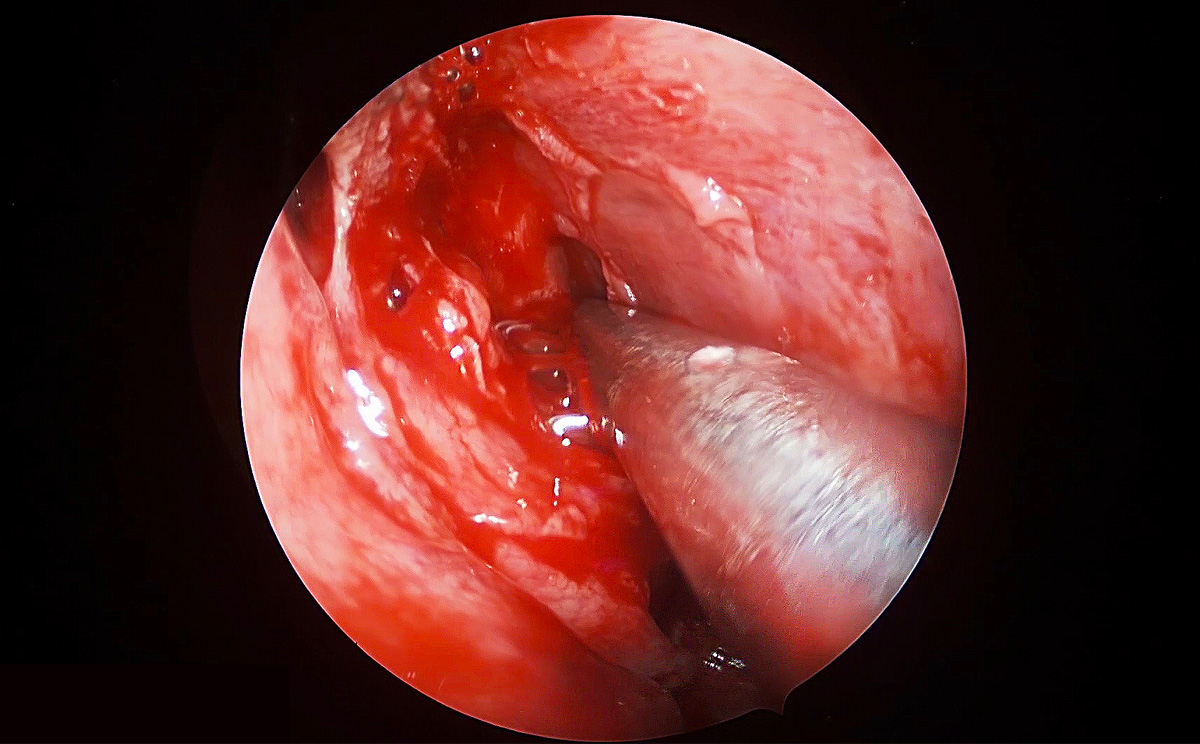

4K超高清內窺鏡攝像系統(tǒng)在腦垂體瘤切除術中的精彩表現(xiàn)

此次手術采用內窺鏡下經鼻進路行腦垂體瘤切除術,使用機器益柯達4K超高清內窺鏡攝像系統(tǒng),分辨率可達3840X2160P,是全高清內窺鏡分辨率(1920X1080P)的4倍,該產品具有出色的色彩還原功能,能夠精細的顯示手術中的細微血管、神經、筋膜層次,使手術更精準、安全。